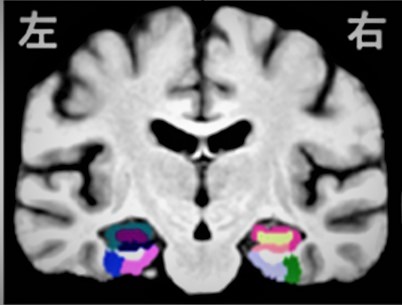

"Mild exercise improves sifting between similar memories"